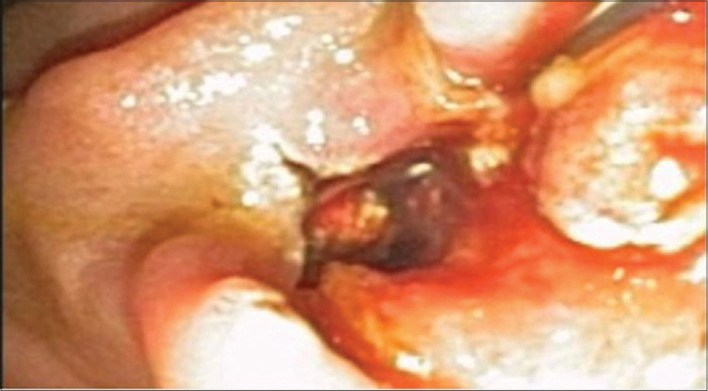

Abstract: Migration of cholecystectomy surgical clip into the common bile duct with subsequent stone formation is a rare phenomenon, one which may lead to complications including obstruction, pain, nausea, vomiting and fever. The mechanism of migration is largely unknown but may result from a combination of factors including necrosis, intra-abdominal pressure or poor surgical technique with migrated clip serving as a nidus for stone formation. We present a 55-year-old woman with clip-induced stone impacted at the distal common bile duct 12 years post-cholecystectomy and a review of the literature related to cholecystectomy clip stone formation. In addition, we reviewed relevant English language case reports and literature reviews by searching PubMed using search terms 'stone', 'clip', 'cholecystectomy' and 'biliary'. There was no limit to the date of publication. Our study found 68 unduplicated cases of clip-induced stones which had a wide range of onset and presenting systems. Further research is needed to identify risk factors, methods of prevention and benefits of early detection screening.